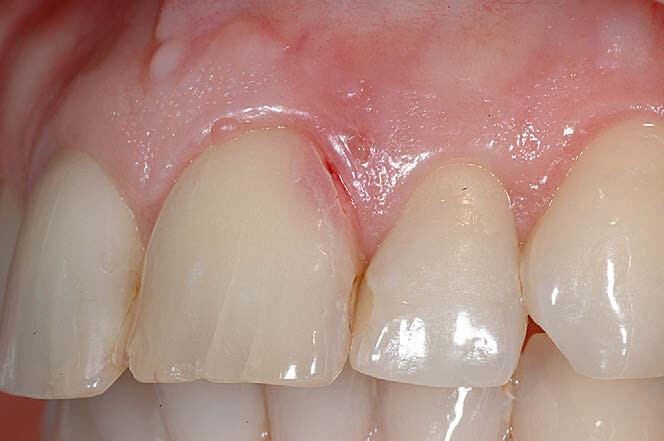

During an examination, dental hygienists may notice what seems to be a lightly discolored pink spot located at the cervical region of a tooth or even found in the crown showing through (figure 1). In both locations, this appearance, or “pink spot,” has to do with granulation tissue present underneath the enamel.

ECR can be differentiated from root caries due to its pink hue and tactile sensation. During the examination, you will find that the dentin surrounding an ECR lesion is usually hard, whereas decay/caries typically feels sticky. When a clinician performs probing around this type of lesion, it will typically bleed—often profusely—because of the highly vascular granulation tissue, a result of the resorptive process.